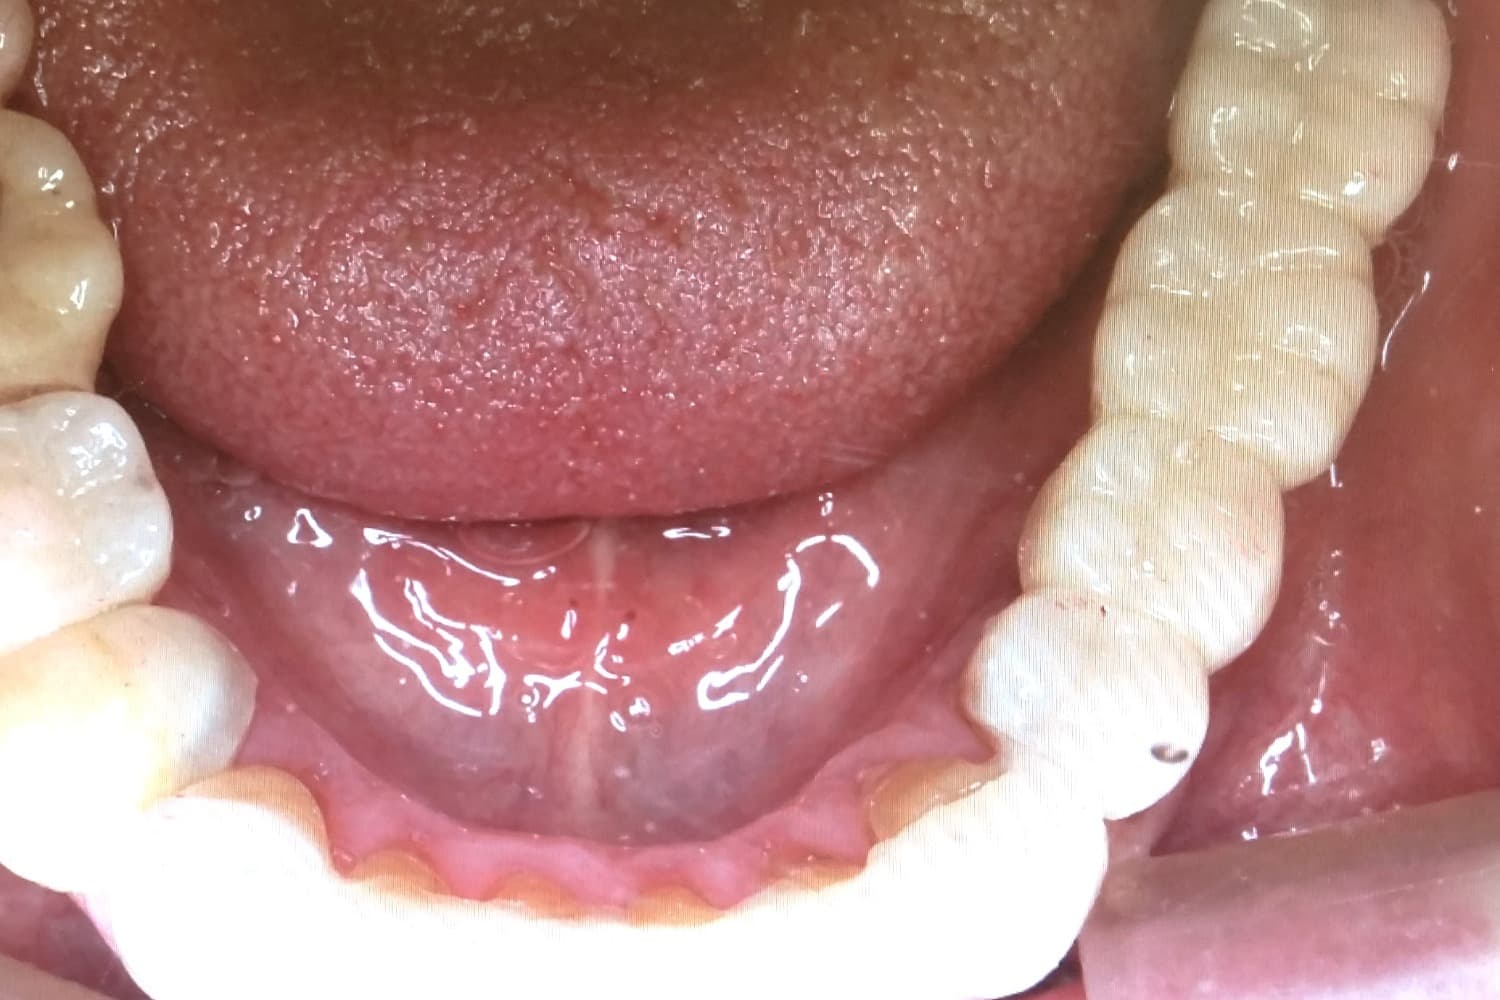

左下奥歯3本欠損部位のインプラント治療による修復

After

左下奥歯3本の欠損部位をインプラント治療により修復をおこなう

年齢

40代

性別

女性

主訴

左下の歯がない箇所をインプラント治療したい

治療期間

4ヵ月

治療回数

5回

費用

825,000円

副作用・リスク

・骨の質や全身疾患によりインプラント体が骨と生着しない可能性がある ・術後に患部が腫れたり痛みが生じたりする可能性がある